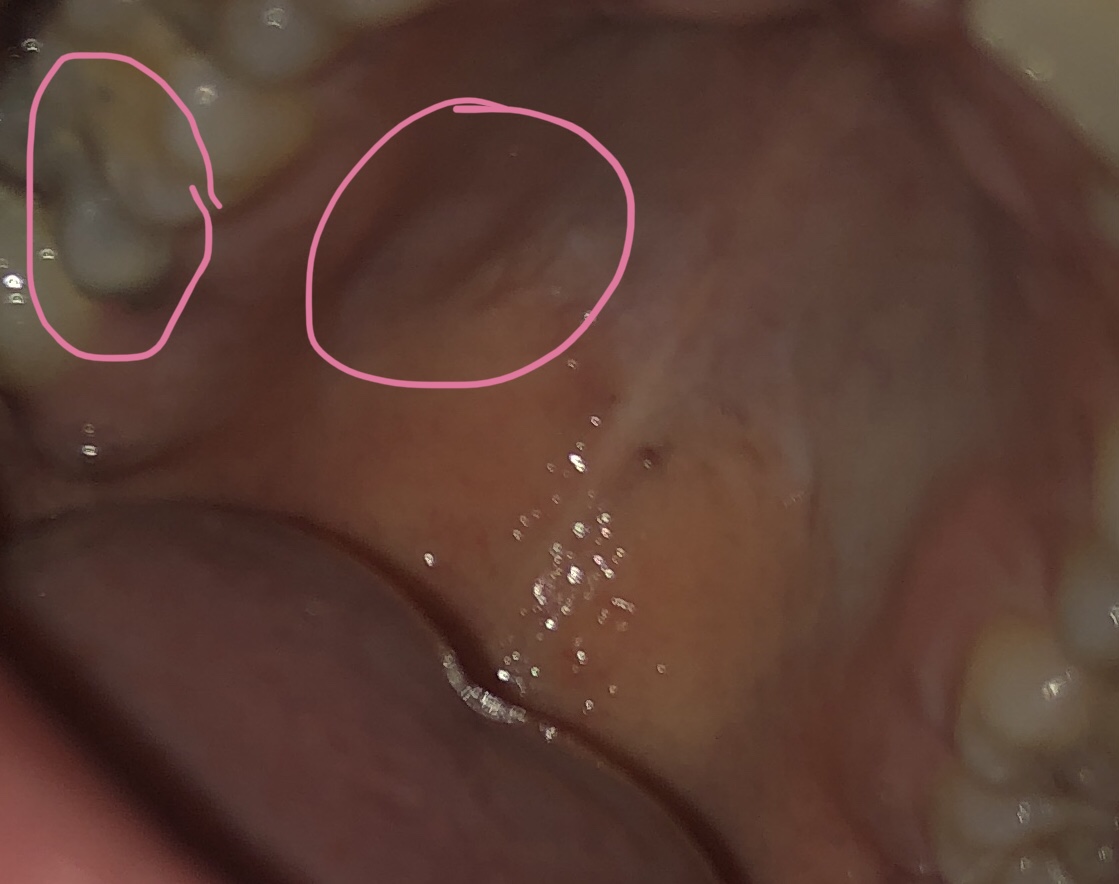

ahojte, ospravedlnujem sa za “foto”, len by som sa chcela poradit.

asi dva tyzdne dozadu ma neskutocne zacal bolet zub, preslo to asi po dvoch dnoch strasnej bolesti, v noci, stale. vcera ma to zacalo boliet znova a vsimla som si ze v takomto stave mam zub.

ano, je z neho len polovica a je totalne zly, az sa mi zuby posunuli lebo je z neho len polka.

ani ma nenapadlo si pozerat do ust, kedze ostatne zuby mam v poriadku. vsimla som si ale take male napuchnute miesto na podnebi, ktore ma pri dotyku neskutocne boli, a ide to k tomu zubu.

buduci tyzden idem k zubarovi, len sa chcem spytat, ci je to normalne, myslite ze to moze byt kvoli zapalu? pri dotyku to akoby splaskne ziadna hrcka to nie je, no ta bolest zuba mi vystreluje sz do oka, ucha, nechapem ako som si to nevsimla 🥺